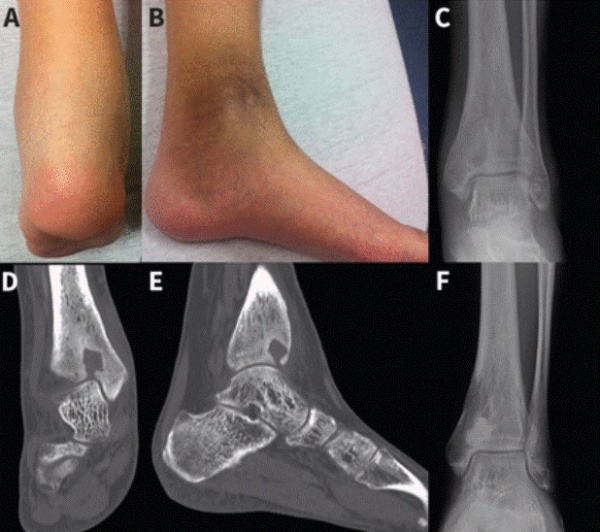

Отек и гиперпигментация левой щиколотки у 27-летнего мужчины с абсцессом Броди (A, в). Рентгенограммы (C, F) и компьютерные томограммы (D, E) показывают поражение дистального отдела большеберцовой кости.

• Рентгенография. В типичных случаях на изображениях видна единственная изолированная округлая костная полость правильной формы, длина которой соответствует длине кости. Полость окружена полосой остеосклероза. Метафиз немного утолщен за счет слоев надкостницы.

• Компьютерная томография. Это подтверждает наличие внутрикостного кистозного образования, окруженного зоной окостенения, яркой периостальной реакции со склеротической трансформацией.